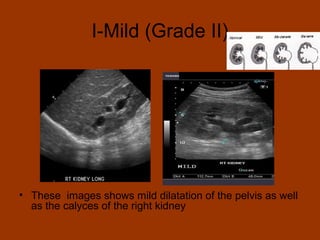

I-Mild (Grade II)

• These images shows mild dilatation of the pelvis as well

as the calyces of the right kidney

I-Mild (Grade II) •These images shows mild dilatation of the pelvis as well as the calyces of the right kidney